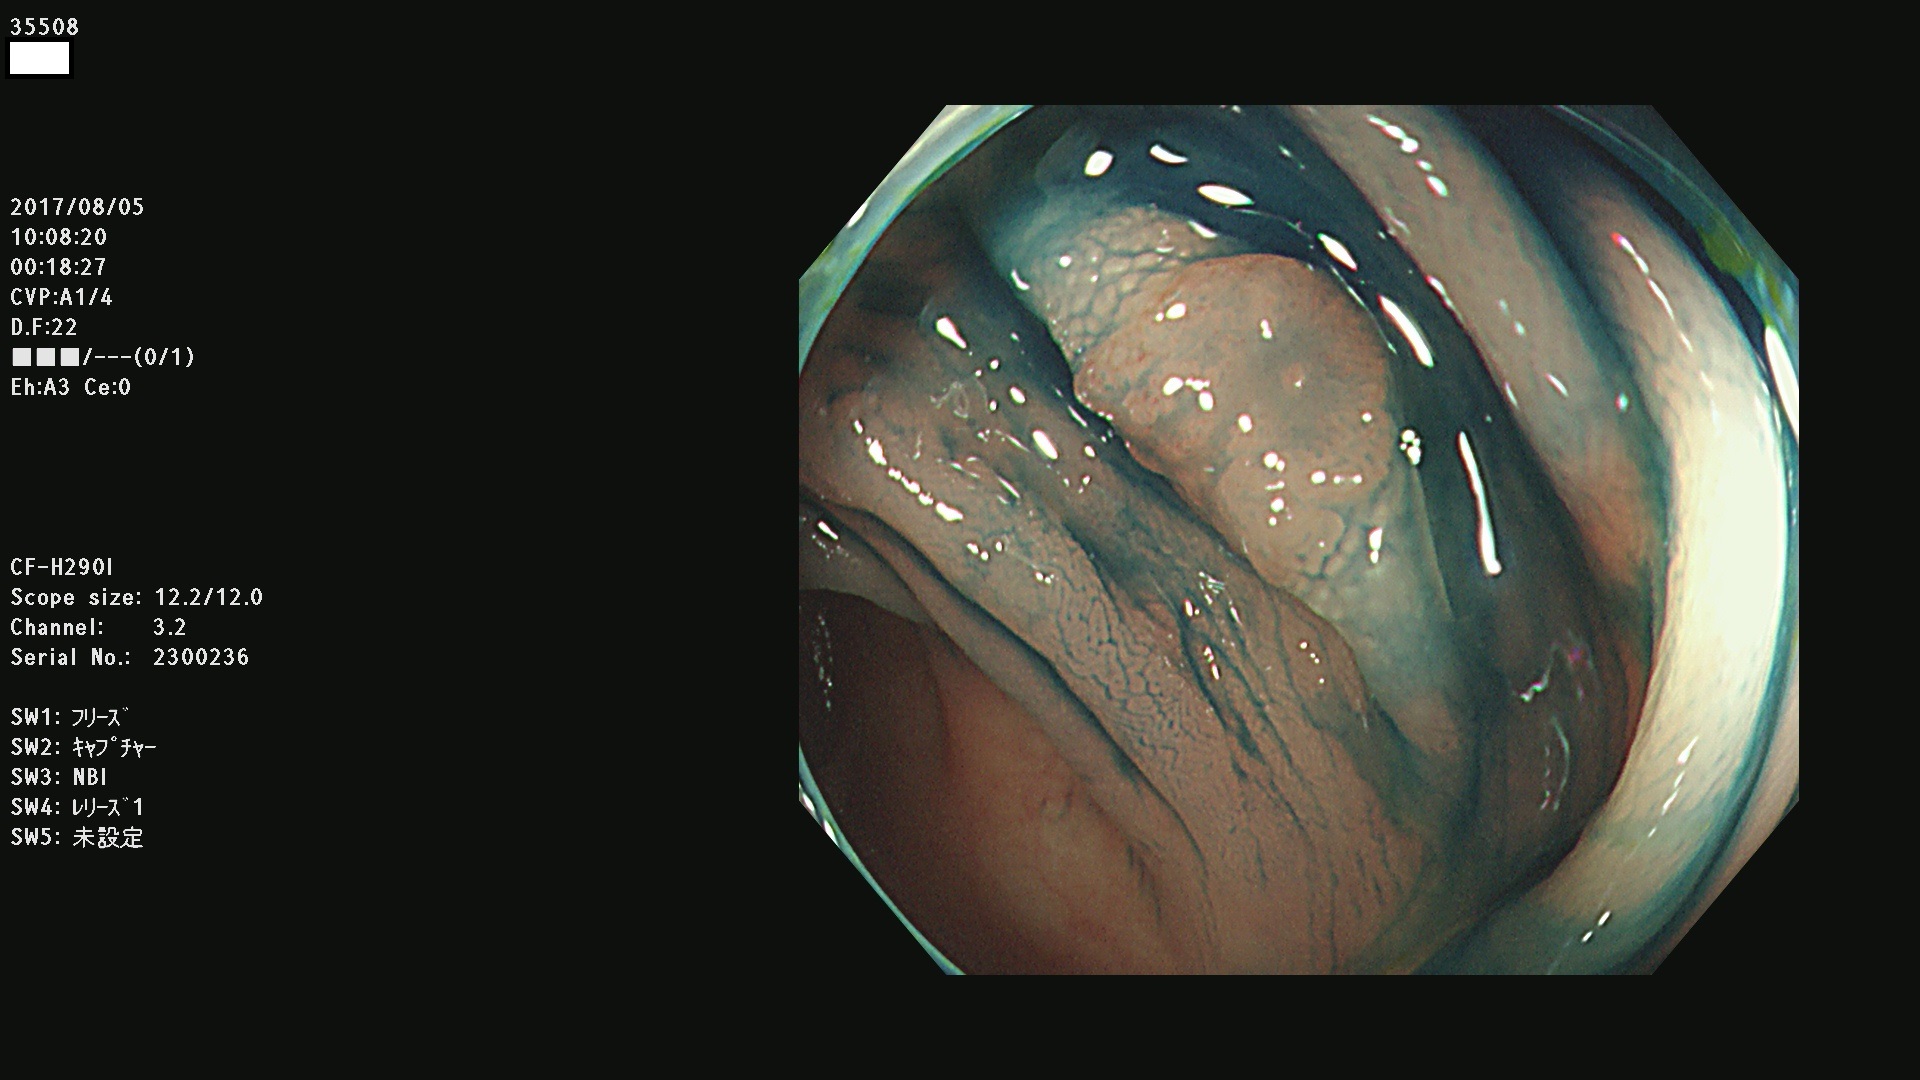

上記100名より抽出した平坦・陥凹型腺腫・SSAP(=癌化の危険が高いが見落としやすい病変)の内視鏡写真

35500 35501 35502 35506 35508 35509 35511 35514 35515 35516 35517 35520 35521 35522 35523 35524 35525 35526 35528 35532 35535 35536 35539 35542 35544 35545 35547 35548 35550 35553 35556 35559 35560 35561 35562 35563 35564 35567 35569 35570 35571 35578 35581 35584 35585 35587 35588 35589 35590 35592 35593 35594 35598 35599・・・・・の54名